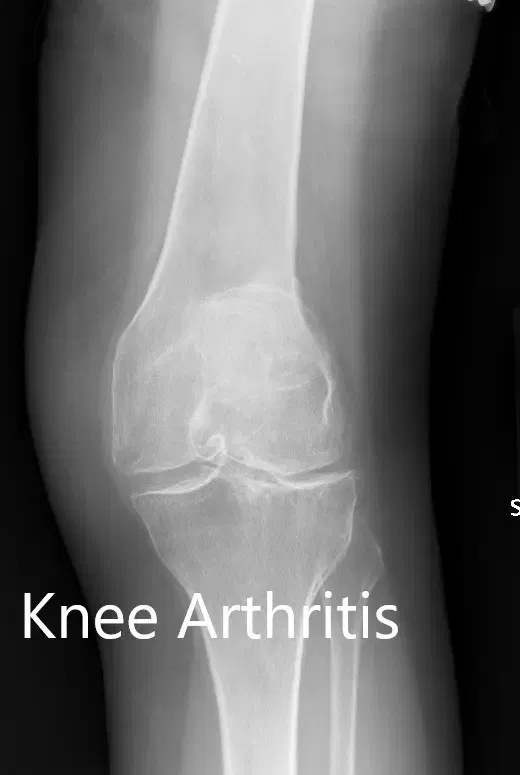

Los estudios de imagen realizados revelaron osteoartritis tricompartmental severa en ambas rodillas. Teniendo en cuenta que su estilo de vida limitaba el dolor de rodilla y el agotamiento de opciones conservadoras de manejo, le recomendaron un reemplazo bilateral de rodilla. Se le consideró candidato para un reemplazo total de rodilla personalizado. Él estuvo de acuerdo con el plan.

Radiografía preoperatoria que muestra la vista AP de la rodilla izquierda y la derecha respectivamente

Radiografía preoperatoria que muestra las vistas laterales de la rodilla derecha e izquierda respectivamente